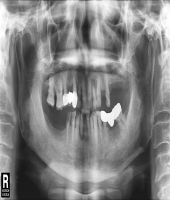

| ● 진료과목 : [임플란트] 치아상실 후 임플란트

| ● 내용 : 다수 치아의 상실 후 임플란트 치료 |